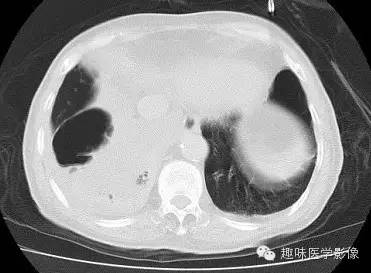

双肺多发无壁低密度区,以右肺下叶底部为主。右肺下叶见大片不规则实变阴影伴多发空洞影,实变肺组织内见支气管气象,右肺下叶支气管局部显示不清。纵隔内见淋巴结。右侧胸腔内见积液影,邻近胸膜肥厚。主动脉、冠状动脉钙化。

右肺下叶肺脓肿、肺炎伴胸腔积液,肺气肿、肺大泡。

右胸廓变小,心影右移;右肺下叶多房性空洞,空洞内未见明显液平面,右下肺病变应该是下叶阻塞性肺炎,实变肺组织内见支气管气像,邻近胸膜增厚,并合并胸腔积液,支持肺脓肿。